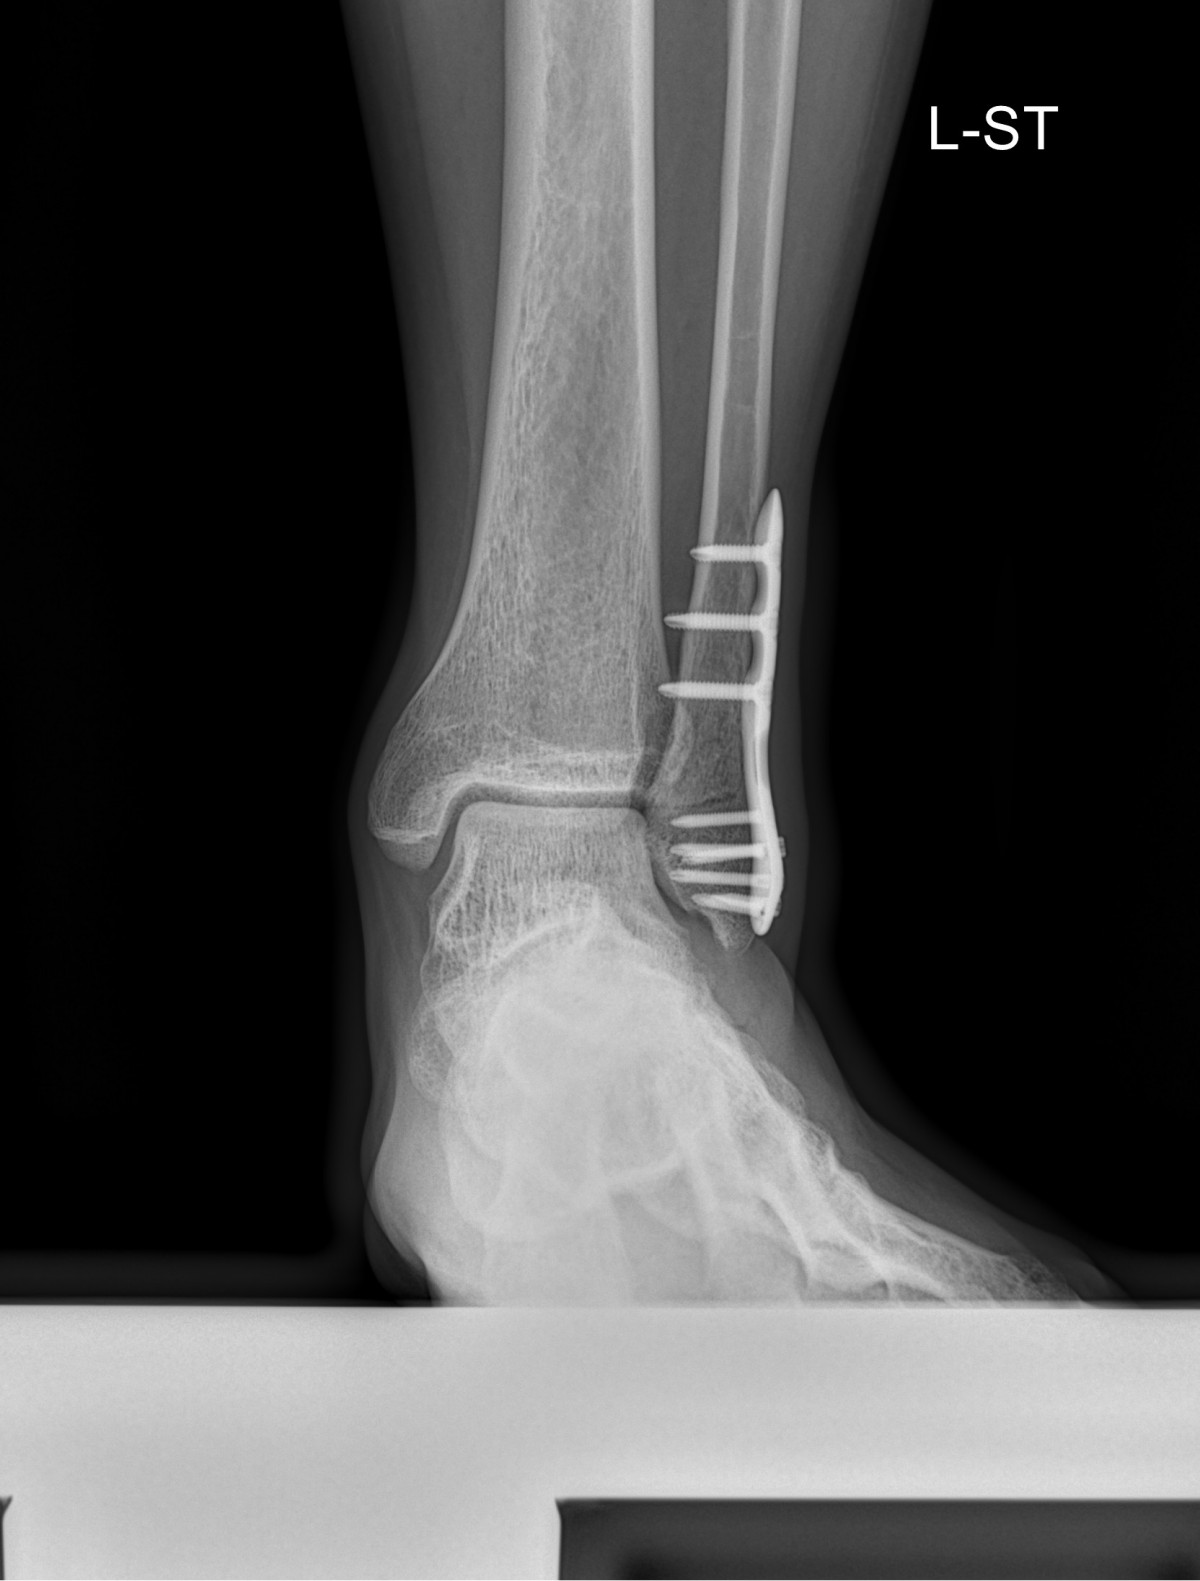

이재상원장님 발목 골절 수술 장용O 환자

dae765e4d9ac96aee867c9d6292d8784_1758002884_4295.jpg